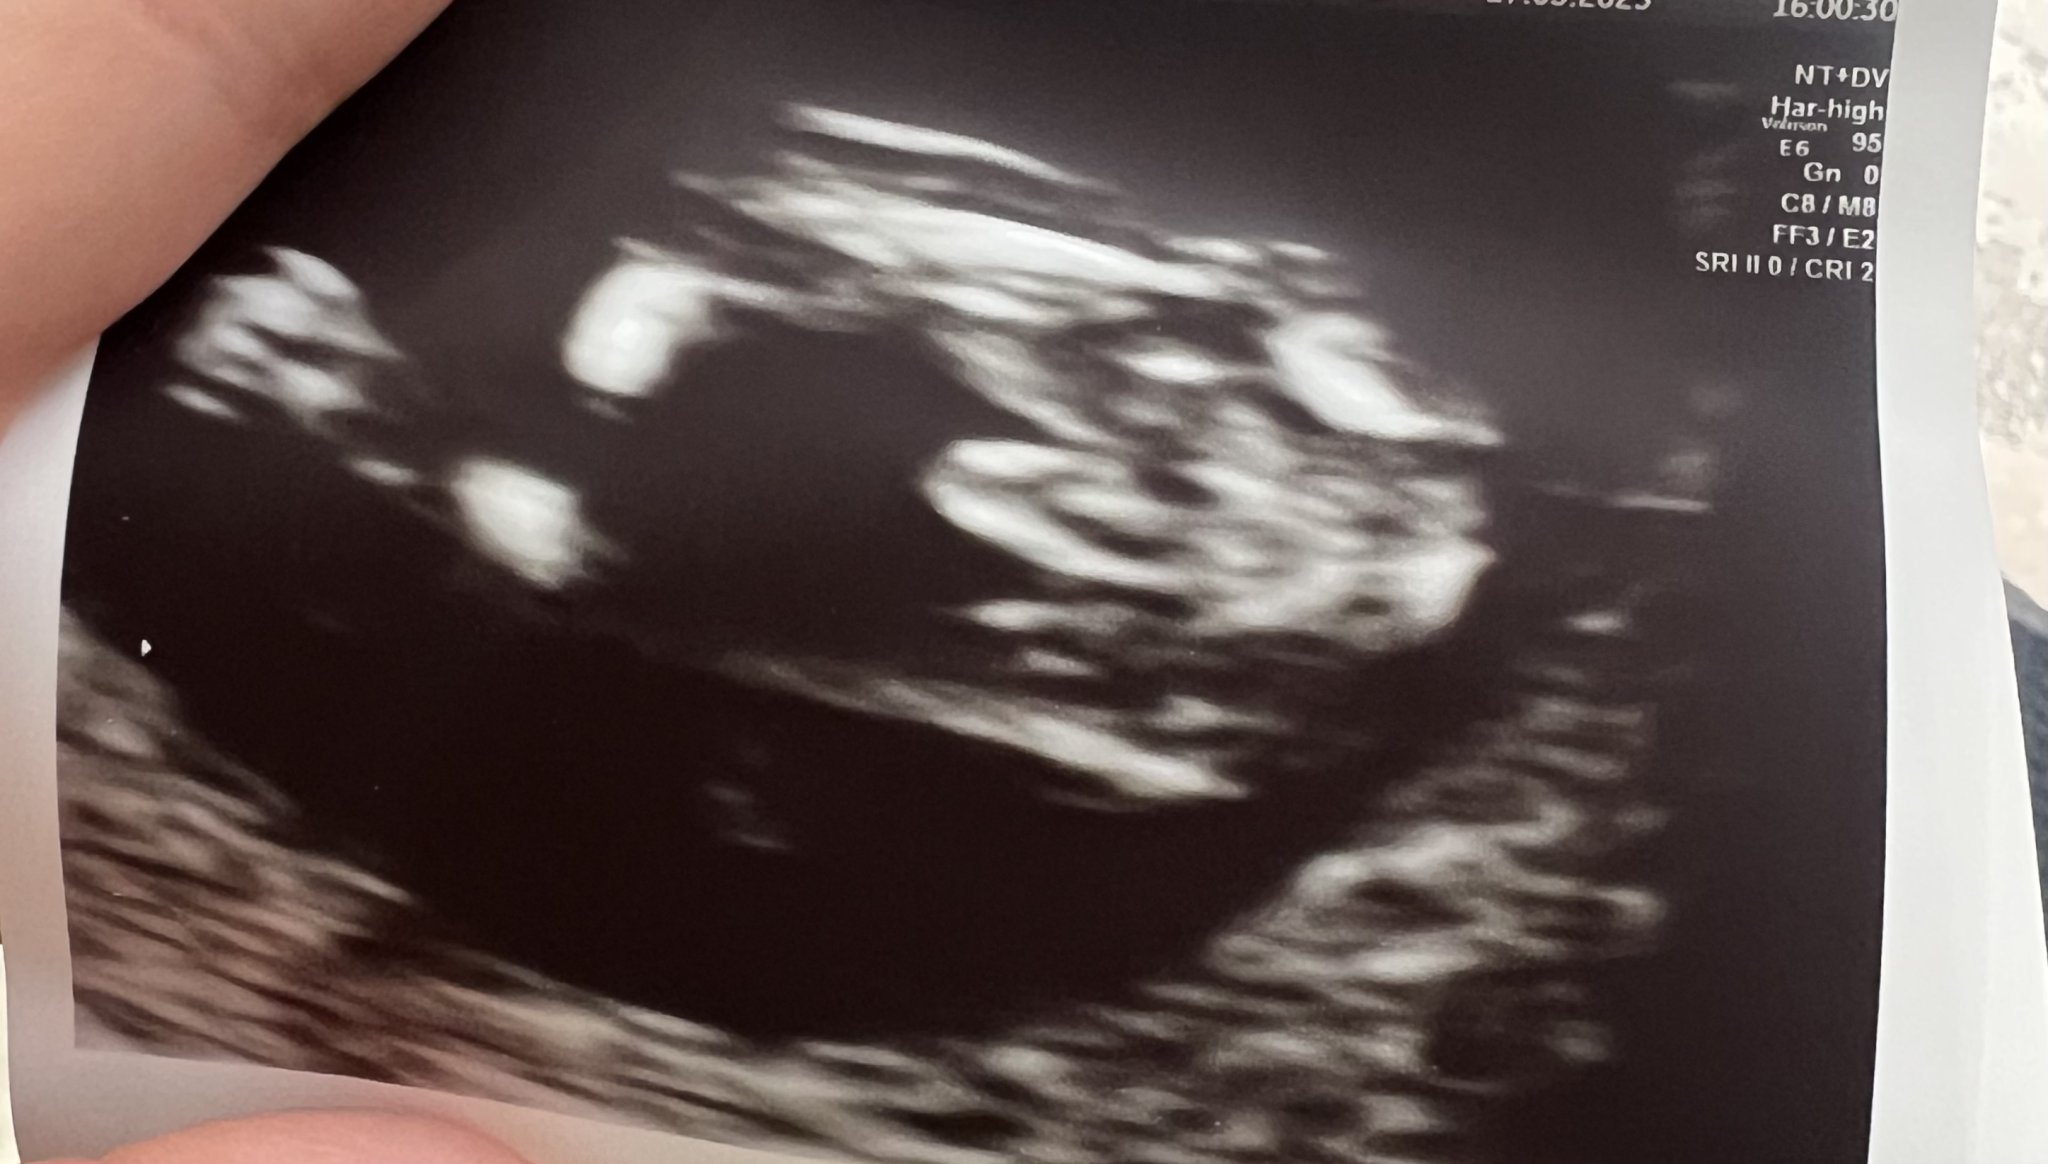

Ей го моя син от прегледа на ФМ. 😂 поисках специално снимка за родата, че много искаха момченце😀